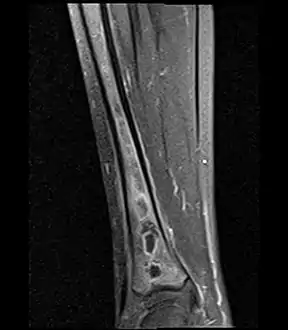

Fat saturated STIR (short tau inversion recovery) image showing hyperintense edema in the calf musculature, marrow edema, and subperiosteal pus. The intramedullary abscess cavity is hyperintense as well.

Coronal fat suppressed STIR image showing, bone marrow and subcutaneous edema as well as subperiosteal edema. The thin hypointense rim surrounding the intramedullary collection represents the reactive interface between the abscess and the body's attempt to wall it off.

Sagittal T1-weighted fat-suppressed post gadolinium image showing the extent of the multiloculated intramedullary abscess.